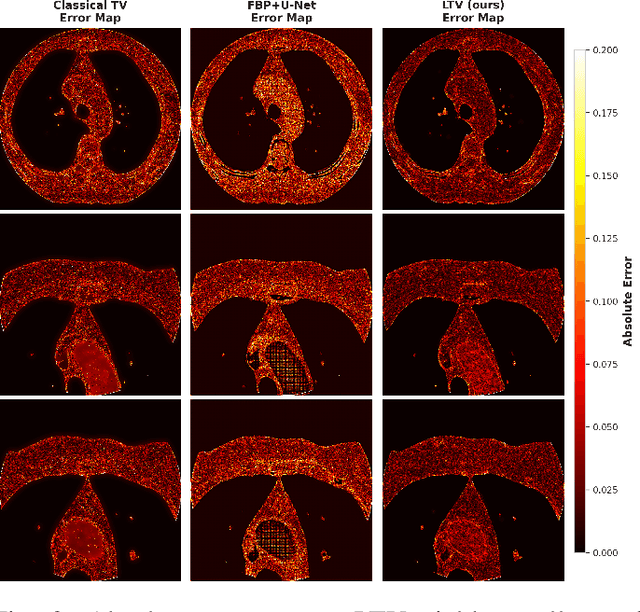

Abstract:Although Total Variation (TV) performs well in noise reduction and edge preservation on images, its dependence on the lambda parameter limits its efficiency and makes it difficult to use effectively. In this study, we present a Learnable Total Variation (LTV) framework that couples an unrolled TV solver with a data-driven Lambda Mapping Network (LambdaNet) predicting a per-pixel regularization map. The pipeline is trained end-to-end so that reconstruction and regularization are optimized jointly, yielding spatially adaptive smoothing: strong in homogeneous regions, relaxed near anatomical boundaries. Experiments on the DeepLesion dataset, using a realistic noise model adapted from the LoDoPaB-CT methodology, show consistent gains over classical TV and FBP+U-Net: +2.9 dB PSNR and +6% SSIM on average. LTV provides an interpretable alternative to black-box CNNs and a basis for 3D and data-consistency-driven reconstruction.